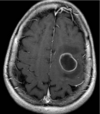

**Ring enhancing lesion** (T1 w/contrast) DDx - abscess, TB, neurocysticercosis, mets, glioblastoma, lymphoma, toxo

Causes of a ring enhancing lesion on CT/MRI

DR MAGICAL